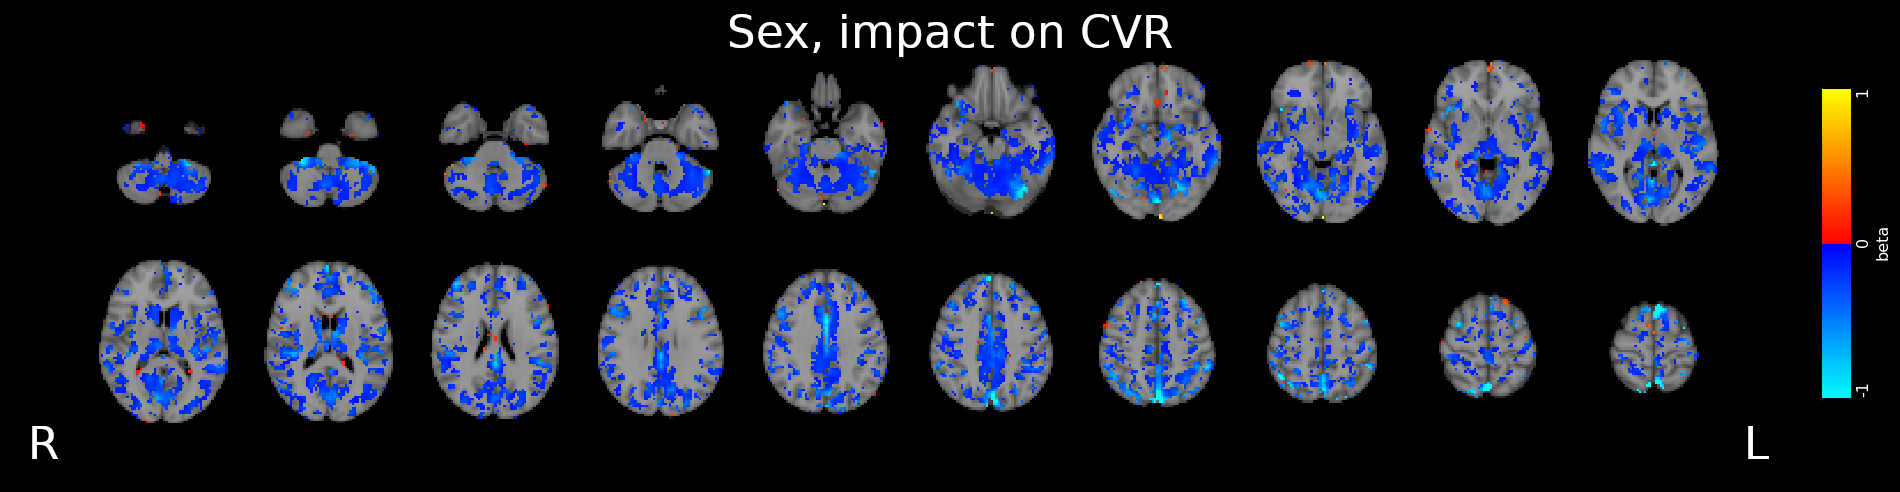

Results: sex

- Females show higher CVR than males in most of the GM

- Previous studies report CVR higher in females¹, in males², or no differences between the two³

- A possible cause of this difference might be related to hormonal changes during the menstrual cycle

1. Kastrup et al. 1997, 1998 (Stroke), Tallon et al. 2020 (Exp. Psychol.); 2. Kassner et al. 2010 (J. Magn. Reson. Imaging)

3. Chen et al. 2021 (Int. J. Imaging Syst. Technol.), Jiménez Caballero et al. 2006 (Rev Neurol)

Results: sex

- Stationary blood pressure changes, expressed as MAP and PP, as well as sex, impact regional CVR estimation differently across sessions and subjects